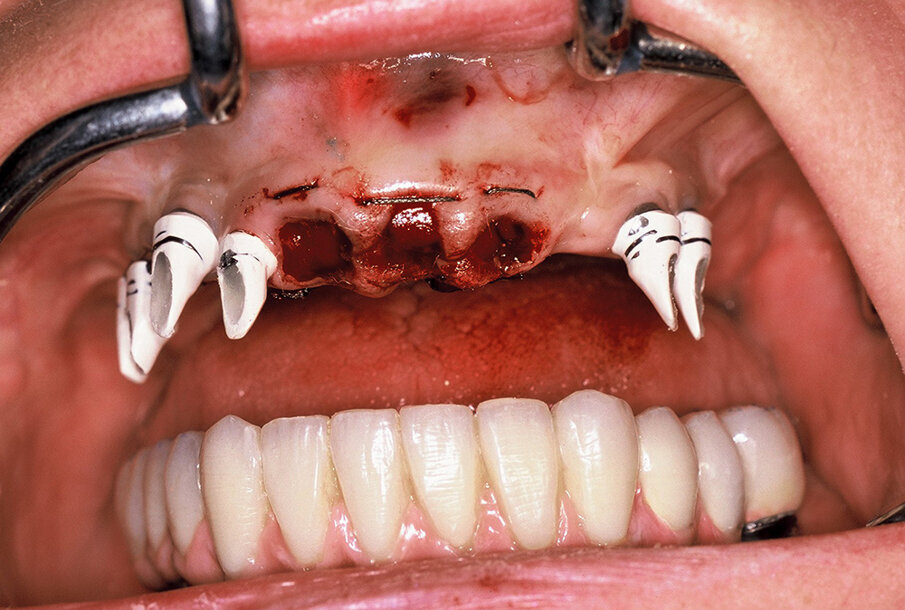

Due to a home accident, the fractured teeth #11-23, 33, 43, and 44 were extracted and an implant was immediately placed in region #44. Open tray impressions were taken using a polyether impression material (Impregum Penta Soft, 3M ESPE) and mounted on a semi-adjustable articulator (SAM 2P, SAM Prazisionstechnik GmbH, Gauting, Germany). For an immediate restoration, provisional abutments were used and temporary covered dentures were fabricated and retained on the provisional abutments (Fig. 6 – Fig. 8).

Fig. 7. Provisional implant abutments and extraction sockets.

Fig. 8. Temporary restorations retained on the provisional implant abutments.